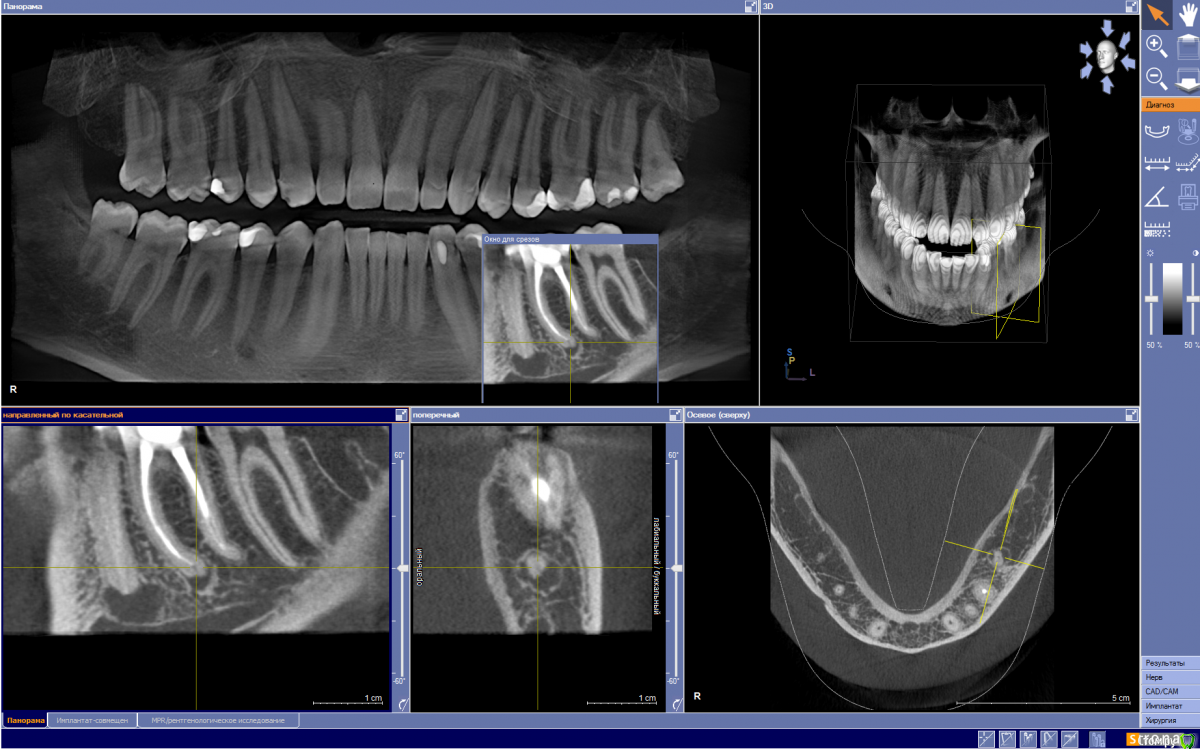

Ситуация: есть два зуба-соседа, оба с леченными каналами. Каналы лечились лет 7 назад, пломбы же над ними менялись около 4 лет назад. Мой терапевт на этом КТ идентифицировала периодонтит левой нижней шестёрки (36) 100%. С левой нижней пятёркой (35) у неё были сомнения, что либо это тоже периодонтит, либо всё же это корень зуба смотрит прямиком в (забыл термин) природную дырку, в которой лежит нерв нижней челюсти (эти дырки симметричны, находятся как раз в районе 4-5 нижних зубов, подбородочное отверстие кажись). Однако показала мой снимок хирургу той же клиники, он подтвердил периодонтит. Ещё должен заметить, что в области этих зубов я ощущаю чувствительность, как-будто там нервы ещё есть в каналах - иногда можно ощутить слааабенькую боль; если же попить вино, то уже боль чуть заметней, такая лёгкая ноющая кислотная боль; холодное даже ощущается - словно зуб освежили после каждого приёма холодной воды. Но тем не менее, врач говорит, что каналы лечены: у 35 прям до самой верхушки корня видно пломбировочный материал; у 36 всё заполнено нормально, однако у верхушки корня как-будто не удалось долечить - там корень с изгибом.

1. Зуб 36, его верхушка: там тёмное пятно. Это кариес?

2. Зуб 35, его верхушка: между пломбой в верхушке зуба и каналами тёмная плоскость на "Поперечном" ракурсе. Это какая-то прокладка или кариес?

3. Зуб 35, его верхушка: в пломбе верхушки зуба на ракурсе "Направленный по касательной" видно чёрную точку. Эмм... ? Воздух?

4. Зуб 47, его верхушка: тёмная область - кариес?